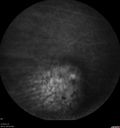

88 year old female with melanosis oculi and 2.5 mm elevated choroidal melanoma. She also has AMD with geographic atrophy. The right eye is the better eye. The left eye had a macular hemorrhage from wet AMD and breakthrough vitreous hemorrhage.